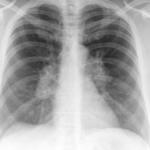

Signs

Album: Signs

Date: 04/28/2014

Size: 29 items

Views: 66600